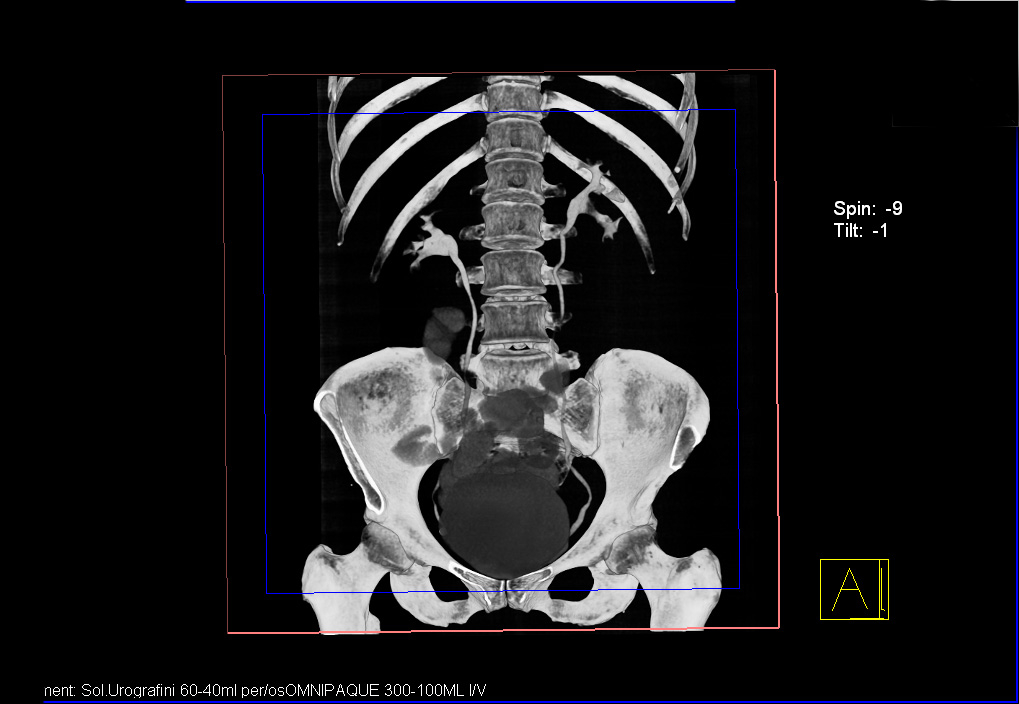

Женщина средних лет, жалоб нет.

УЗИ почек - малый рак. Small RCC.

Позвонили пациентке, она сделала КТ - новообразование подтверждено.